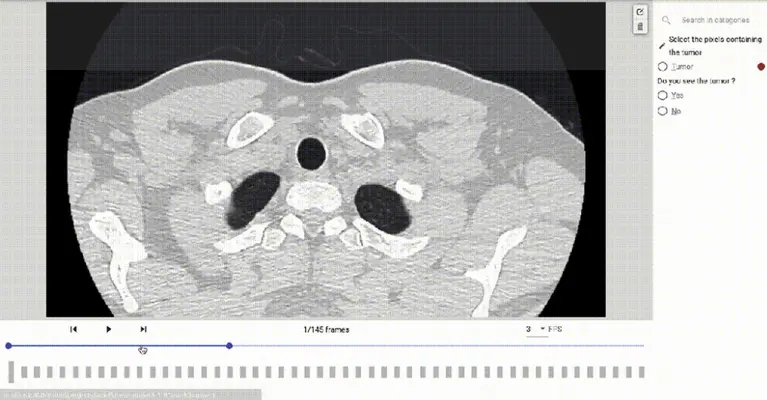

Kili technology makes annotating medical images and reports quick and simple. Import DICOM 2D, 3D CT Scan or MRI data, classify, draw bounding boxes, create polygons or segments to identify suspicious spots on the skin, lesions, tumors and brain haemorrhages. Build your training datasets with highly customizable interfaces that allow you to combine tasks to improve productivity.

Kili Technology manages DICOM 2D, 3D MRI or CT Scan images, and offers specialized interfaces for all annotation tasks related to intelligent document processing in healthcare. This includes medical imaging and NLP, image classification for visual diagnosis, identification of lesions, tumors, cancer cells, entity extraction for medical documents, OCR for medical records, and more.

Add structure to the image with Bounding Box Annotation, Semantic Annotation, Polygon Annotation, Point Annotation, Segment Annotation, Image Classification, and more. We support the DICOM image format for AI in radiology.